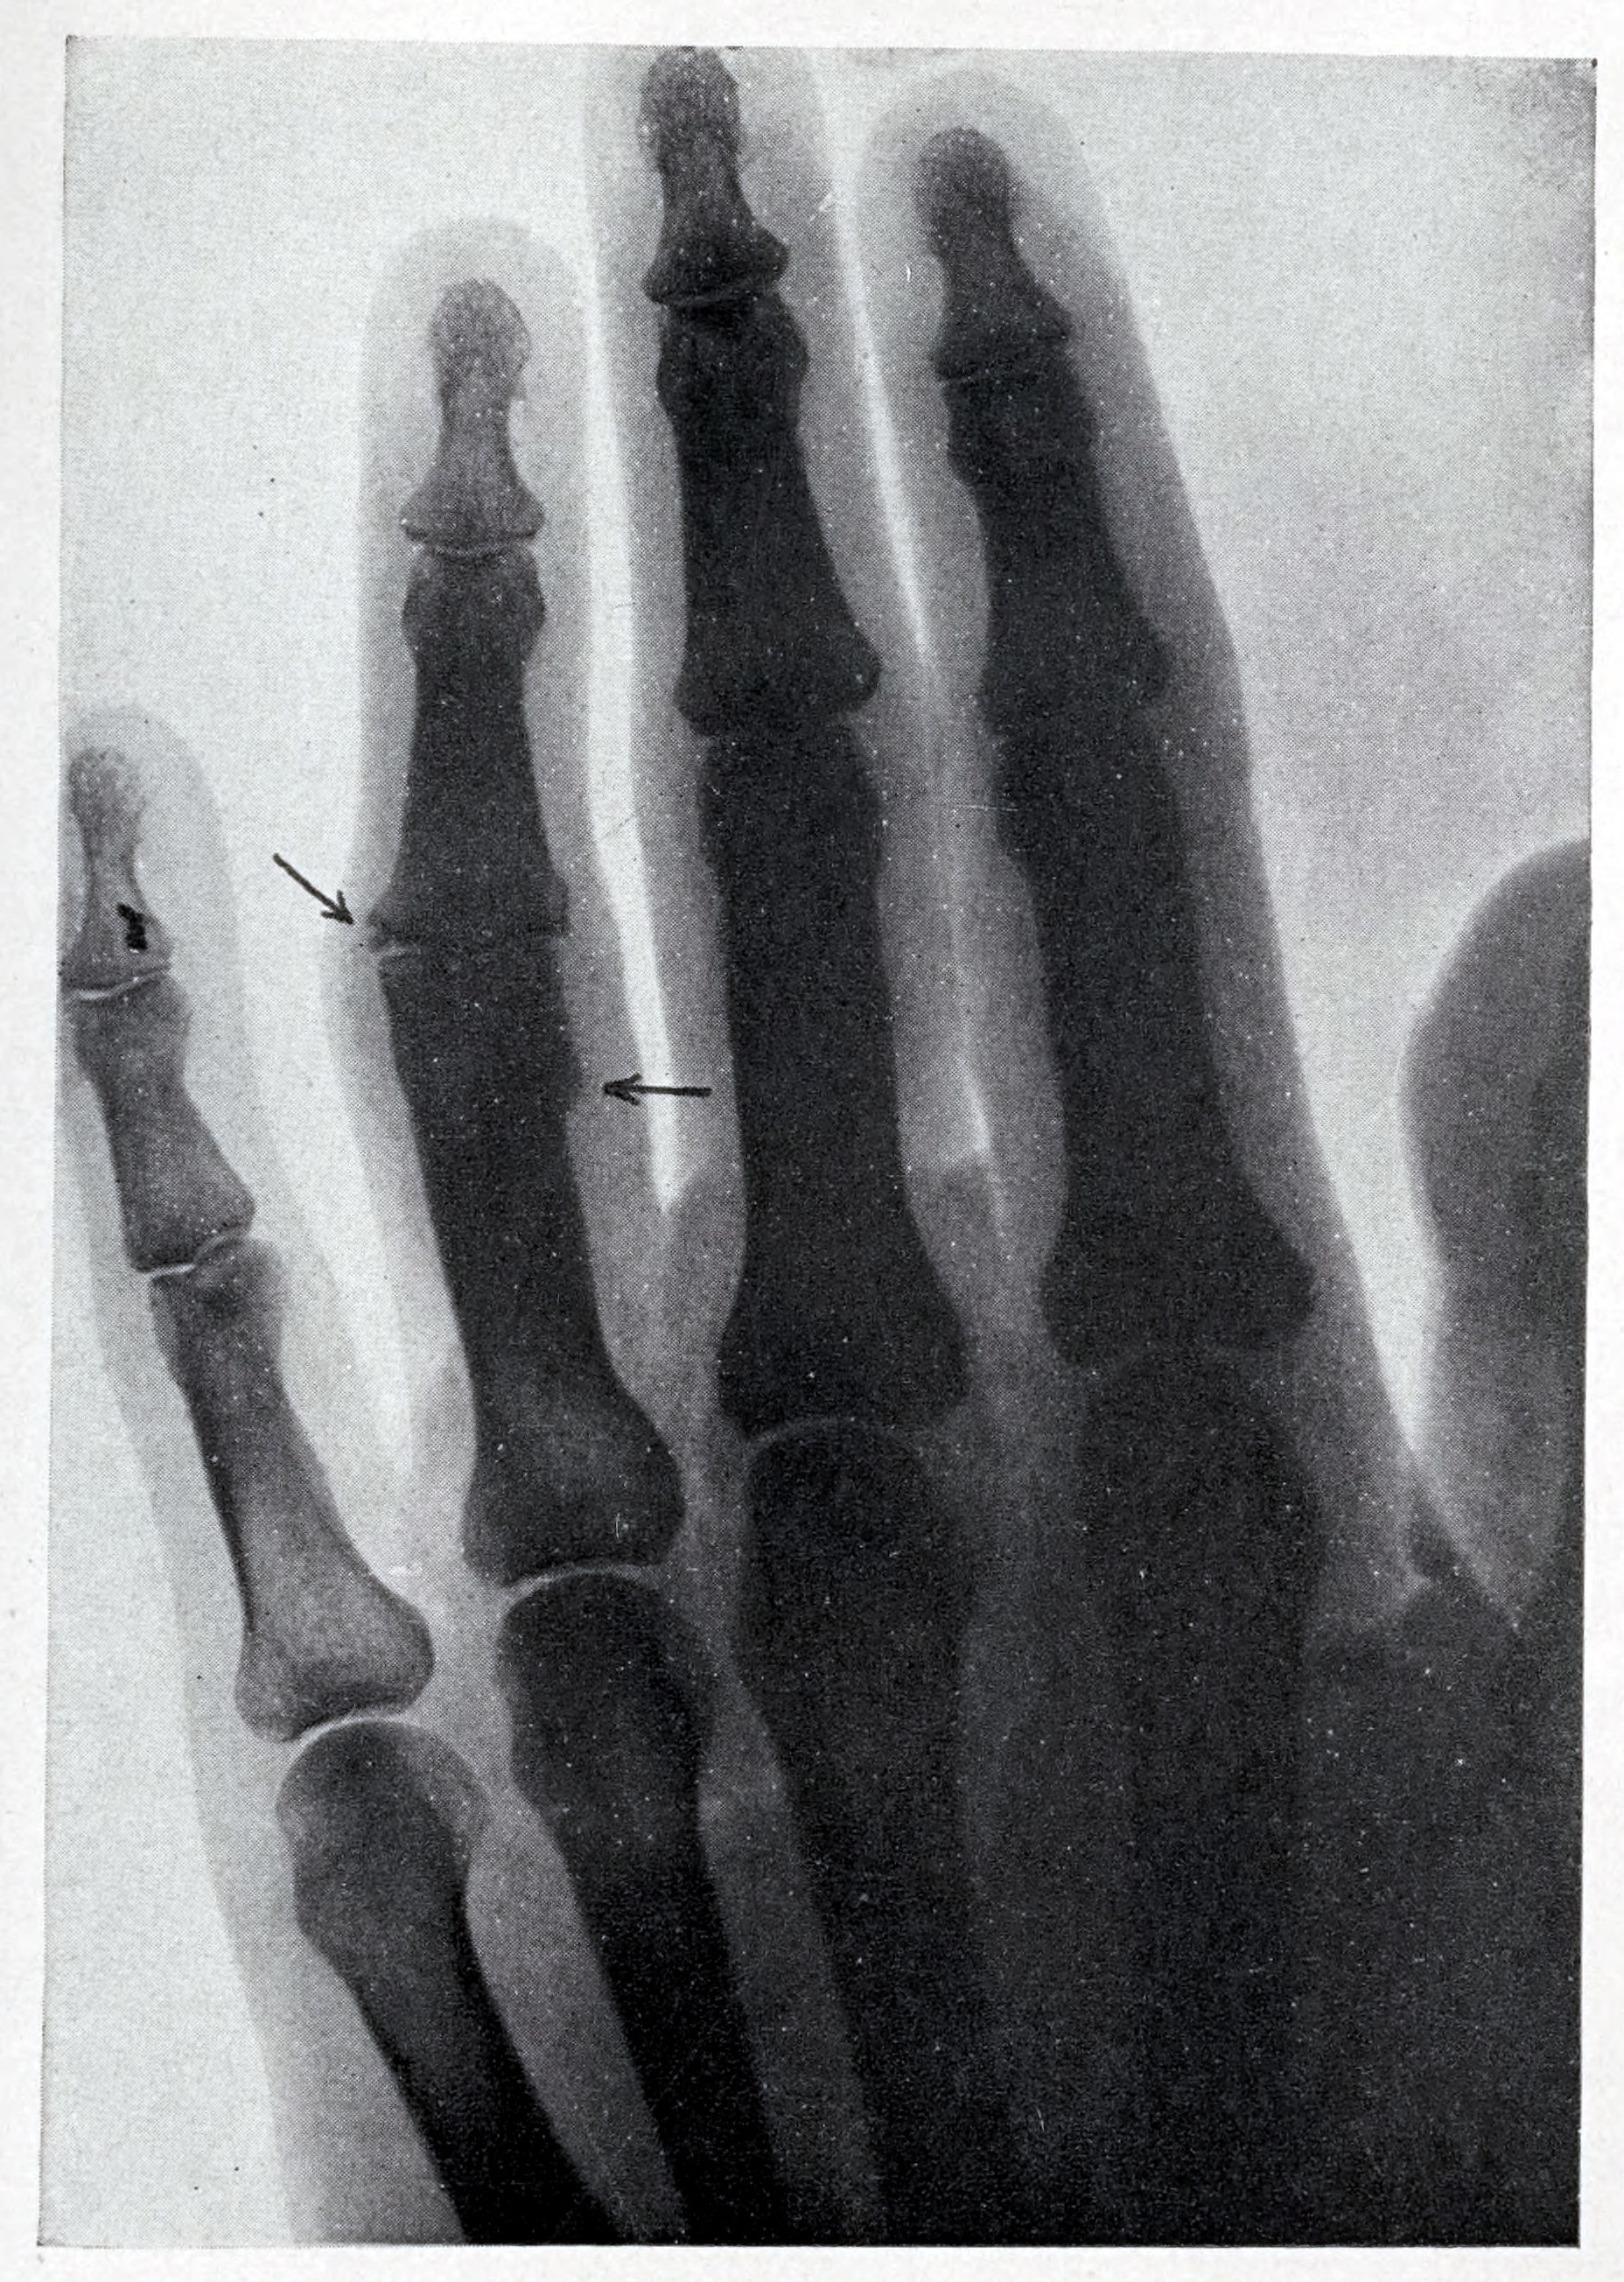

- An X-Ray Photograph of the hand taken with the Outfit shown in Figure 174. The arrows point to injuries to the bone of the third finger near the middle Joint Resulting in a Stiff Joint.